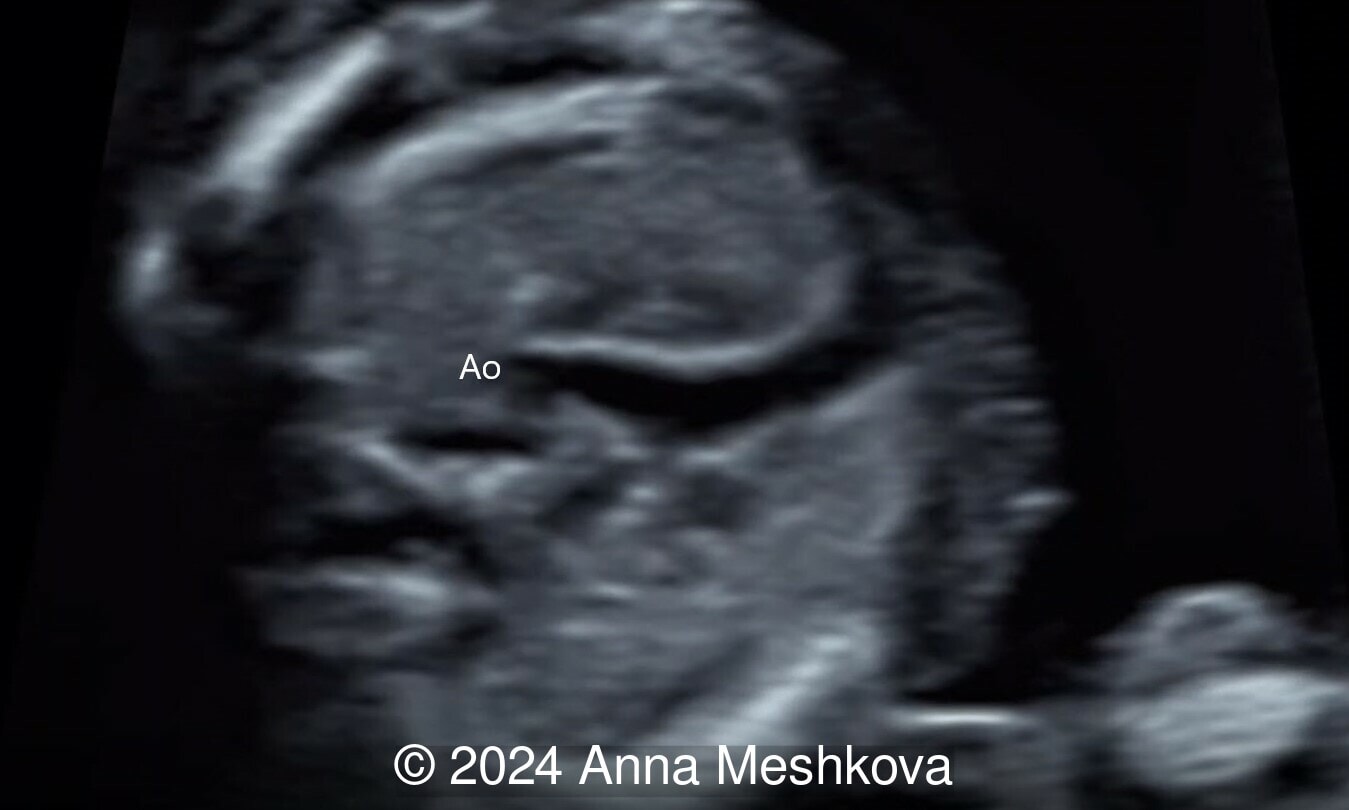

We present a case of D-transposition of the great arteries with ventricular septal defect diagnosed in early pregnancy.

- 3 vessel view demonstrating that the aorta arises from the right ventricle (Video 1,2)

- Sagittal plane through aortic arch shows parallel course of the great vessels (Image 2, Video 6,7)

Transposition of the great arteries is a common cardiac malformation with atrioventricular concordance (normal connection between atria and ventricles) and ventriculoarterial discordance (connection of the great vessels is switched). In our case, both great arteries display a parallel course, with the aorta anterior and to the right of the pulmonary artery (hence the term D-TGA “dexter”). D-transposition of the great arteries (D-TGA) is relatively frequent cardiac anomaly occurring in 5 to 7% of congenital cardiac malformations, with an incidence 0.315 cases per 1000 live births and 2:1 male preponderance.

On prenatal ultrasound, the four chamber view is typically normal, except for an associated ventricular septal defect. The aorta is noted to arise from the right ventricle in an anterior and parallel course to the pulmonary artery. Instead of a 3-vessel trachea view, a single large vessel (the transverse aortic arch) with a superior vena cava to its right is identified (I–sign). On longitudinal views, the aortic arch is seen arising from the anterior right ventricle, giving rise to head and neck vessels and assuming a “hockey stick” orientation as it curves posteriorly. The pulmonary artery assumes the “candy cane” orientation. Before inclusion of the outflow tracts to international fetal cardiac screening guidelines, the detection rates reported only 3 to 17 % of simple transposition of the great arteries. In one series of more than 3000 fetuses undergoing detailed screening for anomalies at 11 to 14 weeks, D-TGA is rarely diagnosed early in gestation [2]. The 3-vessel trachea view with a single great vessel may be helpful in early gestation. Additionally, an enlarged nuchal translucency in the setting of normal fetal chromosomes as well as an abnormal cardiac axis can be associated with conotruncal anomalies, including TGA.